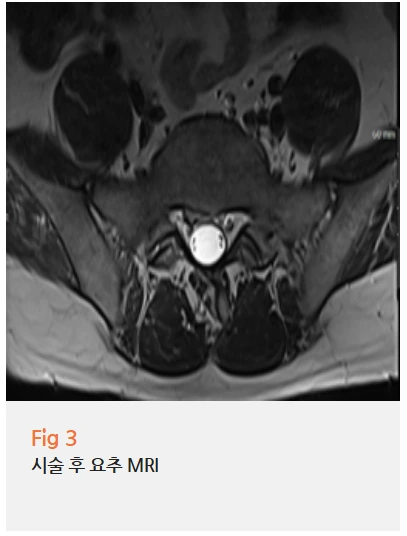

먼저 당일 요추 MRI를 우선 진행했습니다.

네, 요추 4-5번 및 5번-천추 1번 사이의 디스크 탈출이 확인됐어요.

단순 팽윤이 아니라 실제로 신경을 압박하고 있는 상태였고,

특히 우측 신경이 눌려 있는 게 영상에서 명확하게 보였어요.